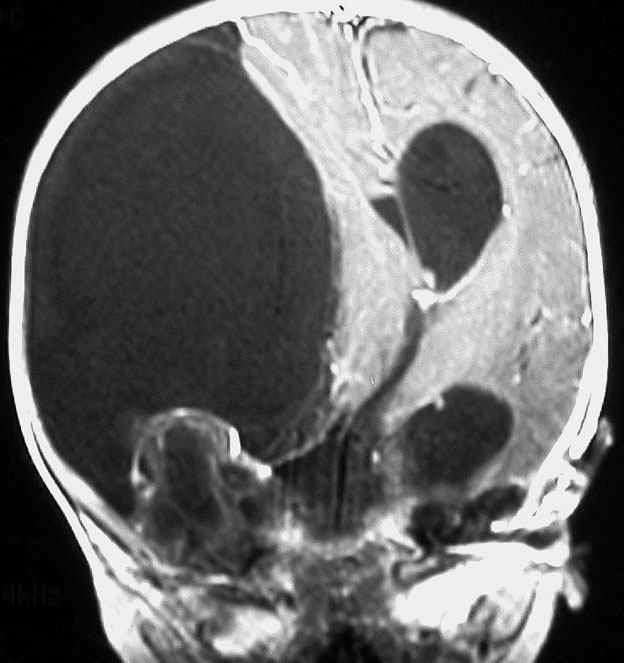

生後5ヶ月の女児に発生した右中頭蓋窩から海綿静脈洞から側頭下窩の成熟奇形腫です。腫瘍のう胞が大きく,右大脳半球の高度の圧排変形がみられます。

のう胞が巨大なので,まずのう胞腹腔シャントをして脳の変形を戻しました。その2ヶ月後に開頭手術で腫瘍を亜全摘出しています。

小児科から抗てんかん薬の投与を受けていますが学習障害などなくて正常です。また腫瘍再発もなく,看護学校へ通学しています。

左上の写真で見えるのは,腫瘍内部にあった小脳組織です。内胚葉,外胚葉性組織など多様に分化した組織が混入しています。

乳児の先天性奇形腫は手術摘出だけで治療できる良性の腫瘍です